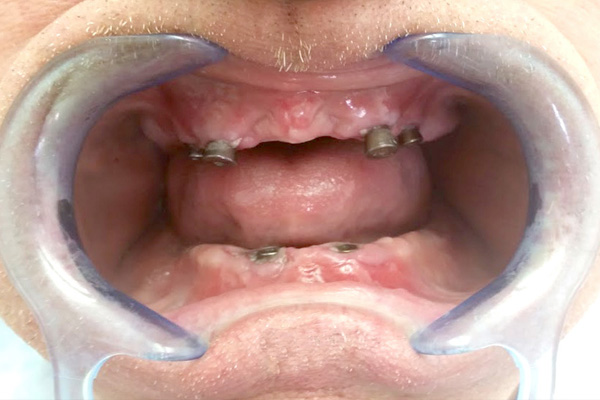

Dentures on implants